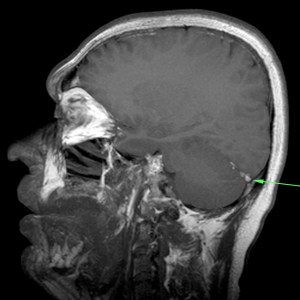

Se decide realizar una RM y una venografía RM para descartar una TVC. Ante el mal estado de la paciente, la cual no colabora, solo se puede terminar realizando secuencias FLAIR y Difusión.

4- RESONANCIA MAGNÉTICA:

La RM combinada con la venografía RM tiene gran sensibilidad no solo para el diagnóstico del TVC sino también para el diagnóstico de lesiones parenquimatosas secundarias, y por ello es la técnica de elección para el diagnóstico de TVC. Sin embargo, en urgencias un TC sin contraste junto con una venografía TC pueden establecer el diangóstico incial de TVC, haciendo innecesario el uso de resonancia en el contexto del diagnóstico urgente en dicho caso.

El protocolo de estudio debe incluir secuencias FLAIR, T1(con y sin contraste), T2, y T2*, así como secuencias de difusión (DRM) y venográficas.

Secuencias convencionales de RM:

- Signos directos: Señal hiperintensa del seno trombosado en T1, que indica la ausencia de flujo y la presencia de material trombosado. Un falso positivo sería la señal hiperintensa por éstasis sanguíneo; para solucionarlo usar estudio contrastado y ver el delta vacío u obtener secuencias en diferentes planos del espacio. Por otra parte, el trombo, al igual que la sangre, presenta cambios en su evolución. En fase hiperaguda, será isodenso con respecto al LCR y por tanto es difícil valorarlo. Para solucionarlo, podemos usar secuencias T1 con contraste y ver el «stop» del flujo o usar secuencias T2 gradiente, ya que es muy sensible a la desoxihemoglobina que contiene el trombos fresco.

- Signos indirectos: Lesiones parenquimatosas que se dan en el 40-70% de los casos. Hay cinco estadios

- Estadio 1: Sin cambios parenquimatosos.

- Estadio 2: Moderado aumento de la presión intracraneal (PIC) con tumefacción, borramiento de surcos y efecto masa. No se altera la señal parenquimatosa.

- Estadio 3: Moderado edema y mayor aumento de PIC. Leve aumento de señal parenquimatosa en T2 ponderado y FLAIR.

Estadio 4: Edema más grave y aumento de PIC (>40 mmHg). Puede haber hemorragia.

- Estadio 5: Edema masivo y/o hemorragia.